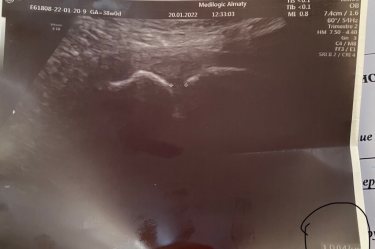

Девочки , спешу Вам сообщить , что расстояние между костями всего 0,47см , то есть даже не 5 мм 😀. Всю ночь переживала)) я препараты кальция не принимала , ногти просто в ужасном состоянии и почему то на 70% была уверена что скорее диагноз подтвердится. Боли в лобке просто не передать словами , стою болит, поворачиваюсь болит, лежу болит , аж походка изменилась (((( (Симфизита нет)

Это значит что могу рожать сама ) симфизит это расхождение лобковых костей которые между собой соединены хрящевой тканью. Если расхождение больше 1 см то делают кесарево, рожать самой опасно. Расходятся из за дефицита кальция , из за гормонов и т д. А так голова ребёнка уже в малом тазу сказали )